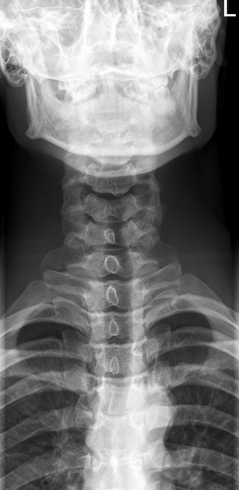

AP Axial C-Spine: Is this Image Good?

No.

Vertebral body of C3 is partially superimposed by base of skull

Incorrect CR angle (caudal) produced foreshortening of vertebral bodies and closure of intervertebral joint spaces

Excessive extension superimposed base of skull over upper C-Spine

Correct the angle and adjust head so that a line from lower margin of upper incisors to the base of the skull is perp. to IR

Lateral C-Spine: Is this Image Good?

No

C7 is obscured

C1 anatomy is clipped and spine is not centered

Need to center higher and more anterior

Tilt leads to poor superimposition of zygapophyseal joints

Used AEC but it wasn’t centered to bone (underexposed)